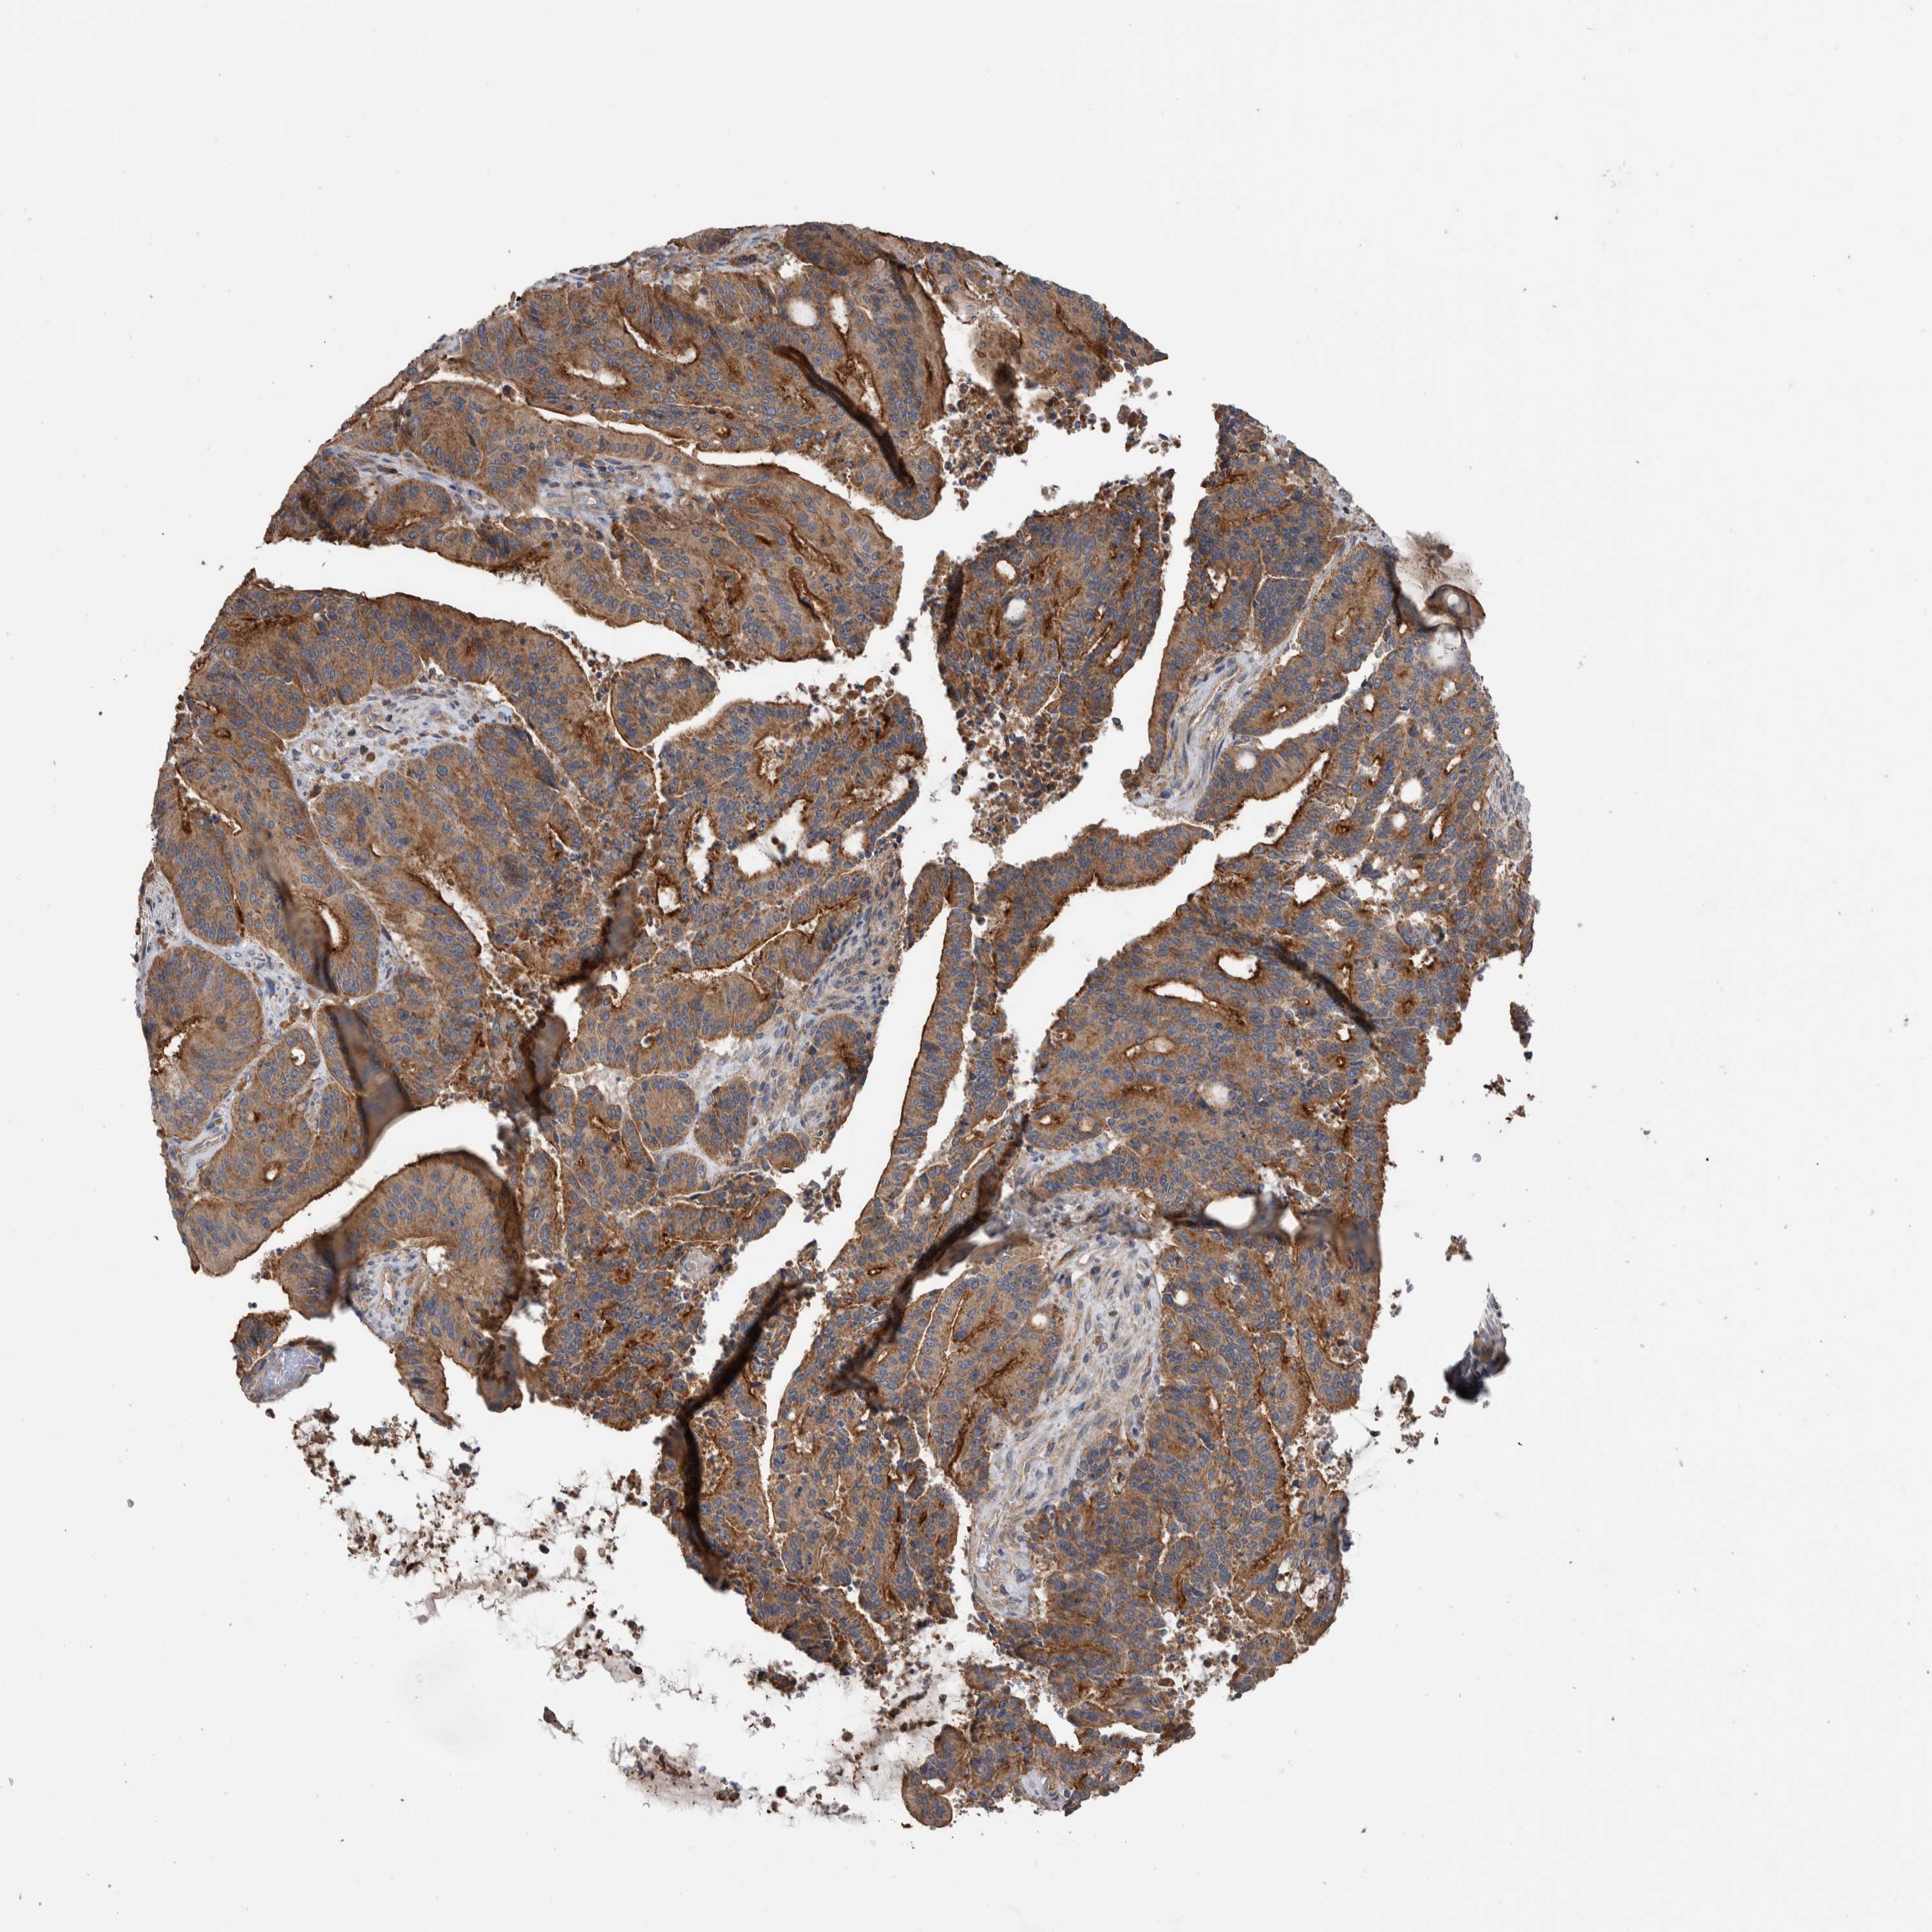

LIVER CANCER - Protein expressioni

A mouse-over function shows sample information and annotation data. Click on an image to view it in a full screen mode. Samples can be filtered based on level of antibody staining by selecting one or several of the following categories: high, medium, low and not detected. The assay and annotation is described here.

Note that samples used for immunohistochemistry by the Human Protein Atlas do not correspond to samples in the TCGA dataset.

Antibody stainingi

Antibody staining in the annotated cell types in the current human tissue is reported as not detected, low, medium, or high, based on conventional immunohistochemistry profiling in selected tissues. This score is based on the combination of the staining intensity and fraction of stained cells.

Each image is clickable and will lead to virtual microscopy that enables deeper exploration of all samples and also displays staining intensity scores, fraction scores and subcellular localization as well as patient and tissue information for each sample.

Antibody HPA023840

Antibody CAB012245

Staining

High

Medium

Low

Not detected

Intensity

Strong

Moderate

Weak

Negative

Quantity

>75%

75%-25%

<25%

None

Location

Nuclear

Cytoplasmic/membranous

Cytoplasmic/membranous,nuclear

Cholangiocarcinoma

Carcinoma, Hepatocellular, NOS